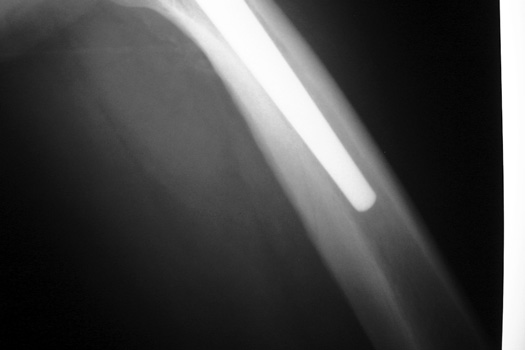

Intraoperative fracture of the femur at the tip of the femoral stem.